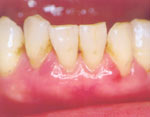

初期の歯周病~軽度の炎症

・歯肉に軽度の炎症 ・歯ブラシなどで出血 ・痛み・腫れはない

このとき自覚症状は殆どありません。成人の約80%以上が歯周病という統計報告があります。

自覚がないまま静かに慢性的に進行していくのです。この状態を放置すると歯と歯茎のあいだの封鎖がこわれ隙間(歯周ポケット)が生じます。この段階で病変を見つけ、早期に適切な治療を行うことが大切です。歯を無くさない、歯周病菌による病気にかからないために見逃さないよう注意しましょう。